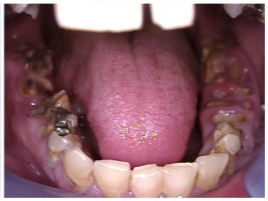

Fig 10. Accumulation of soft plaque is typical of oral hygiene neglect associated with the use of methamphetamine.

Figure 10

Fig 11. Note demineralization of smooth surfaces, carious lesions at the gingival margins, and associated inflammation of the periodontium.

Figure 11

The patient in Figure 10 through Figure 12 was pregnant when she presented for dental treatment. The pregnancy was unplanned and she had had a lack of prenatal care. Continuing meth use during the pregnancy resulted in a positive toxic baby. She stated that she had just stopped using meth and had entered a rehabilitation facility a few days before. She was brought to the author’s clinic with a toothache. Note that as seen in these images, extreme accumulation of plaque, lack of oral hygiene, and severely decayed and missing teeth are classic manifestations in meth users.